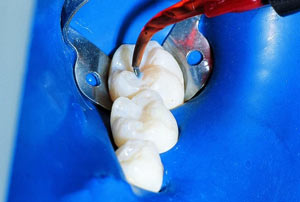

(1)酸蝕20秒,沖洗。圖示為應(yīng)用螺旋毛刷輸送頭,也可以使用藍色輸送頭。

(2)吹干,圖示應(yīng)用的是黑色FX輸送頭,也可以使用藍色輸送頭來。

(3)應(yīng)用窩溝封閉劑。

(4)應(yīng)用光固化等照射。